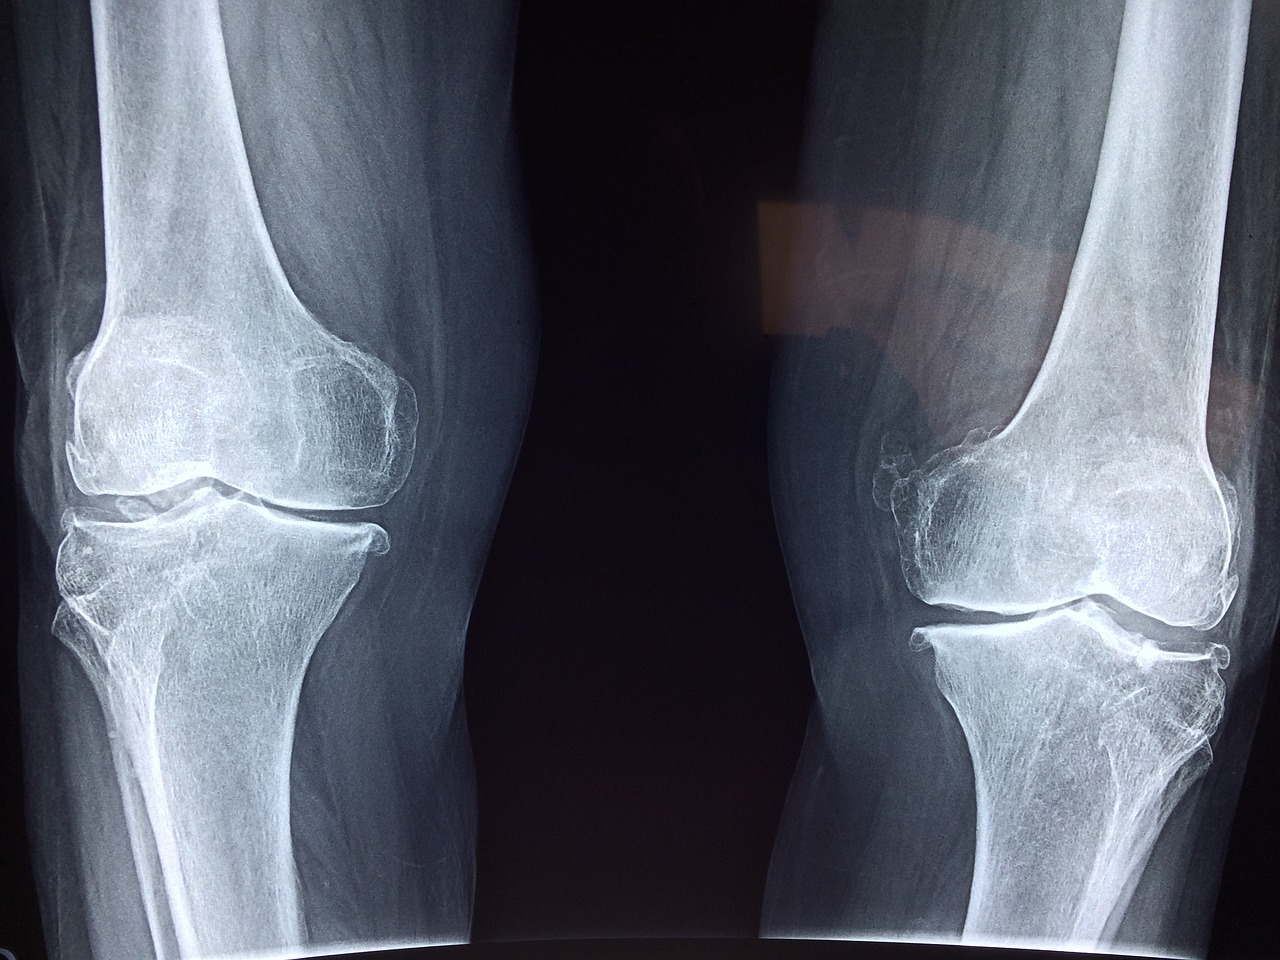

무릎 퇴행성 관절

무릎 안쪽에 통증이 생길 경우 노화로 인한 무릎 퇴행성 관절일 경우가 많습니다.

요즘은 심한 운동 등으로 30대 처럼 젊은 사람들도 퇴행성 관절염 등이 생기곤 하는데요, 연골과 뼈 사이에 마찰을 줄여주는 연골이 파괴되거나 염증이 생기는 경우 발생되며 약물치료나 물리치료 등이 듣지 않을 경우 수술이 필요할 수도 있습니다.